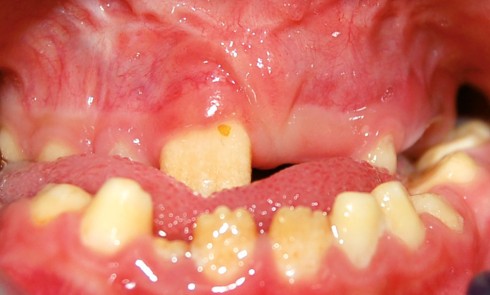

Amélogenèse imparfaite

L’amélogenèse imparfaite (AI) est l’expression d’altérations génétiques associées à des mutations de nombreux gènes codant pour les protéines de l’émail...

L’amélogenèse imparfaite, nom donné à un groupe hétérogène de pathologies affectant le développement de l’émail des deux dentures, a pour...

Définition L’amélogenèse imparfaite est le nom donné à un groupe hétérogène de pathologies caractérisées par un défaut inné du développement...